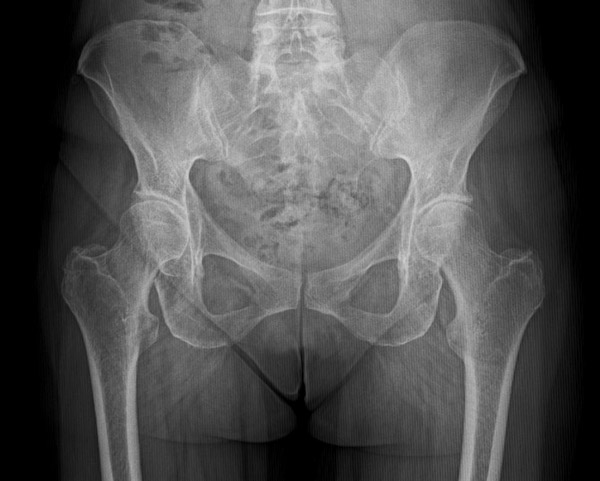

Pre-op X-rays

• Tonnis 1 Hip osteoarthritis ✔️

• Coxa profunda ✔️

• Femoroacetabular impingement Pincer type ✔️

• Anterior hip osteoarthritis ✔️